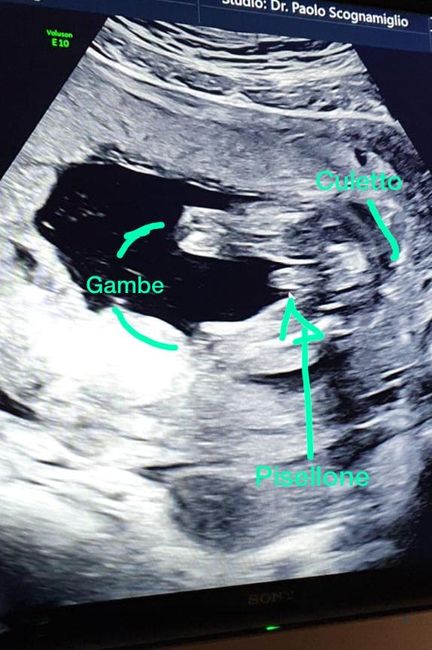

Future Mamme Febbraio 2021

Da Chiara , Il 16 Settembre 2020 alle 20:10

Buongiorno future mamme! Oggi ho scoperto il mio positivo e secondo l’app la DPP è 04/02/2021. Sono già mamma di Giorgia, 1 anno, e non vedevamo l’ora di darle un...